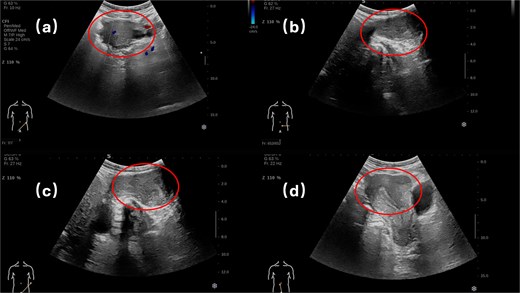

Physical examination revealed a soft, non-tender abdomen without hepatosplenomegaly or shifting dullness; normal bowel sounds were auscultated. A 5 × 5 cm firm, well-circumscribed mass with smooth surface contour and mild tenderness was palpated in the left inguinal region, demonstrating irreducibility and resistance to manual compression. Preoperative imaging modalities—contrast-enhanced computed tomography (Fig. 1) and grayscale ultrasonography (Fig. 2)—suggested a provisional diagnosis of uterine fibroid.

Surgical intervention comprised en bloc excision of the mass with the affected round ligament segment, followed by laparoscopic tension-free mesh hernioplasty (Fig. 3). Histopathological analysis confirmed uterine adenomyoma (Fig. 4). The patient was discharged on postoperative Day 5 following an uneventful recovery.